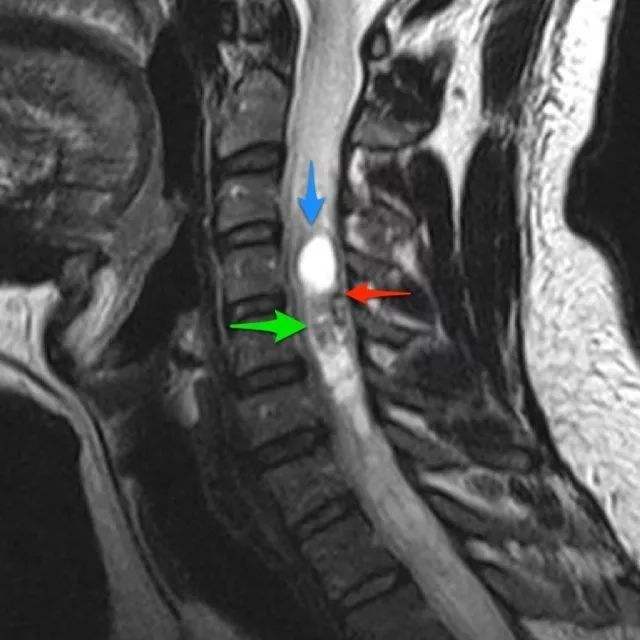

髓内脊髓肿瘤(IMSCTs),如下图所示,是指硬膜内 脊髓肿瘤 的一个亚群,由脊髓内的细胞产生,与相邻结构如神经根或脑膜相对。它们比脑瘤少见得多,据认为占中枢神经系统全部固有肿...

椎管内肿瘤,也称 脊髓肿瘤 ,包括生长于脊髓、神经根、脊膜和椎管壁组织的原发和继发性肿瘤,约占原发性中枢神经系统肿瘤的15%。 椎管内肿瘤的症状和体征在疾病早期常常为隐匿性...